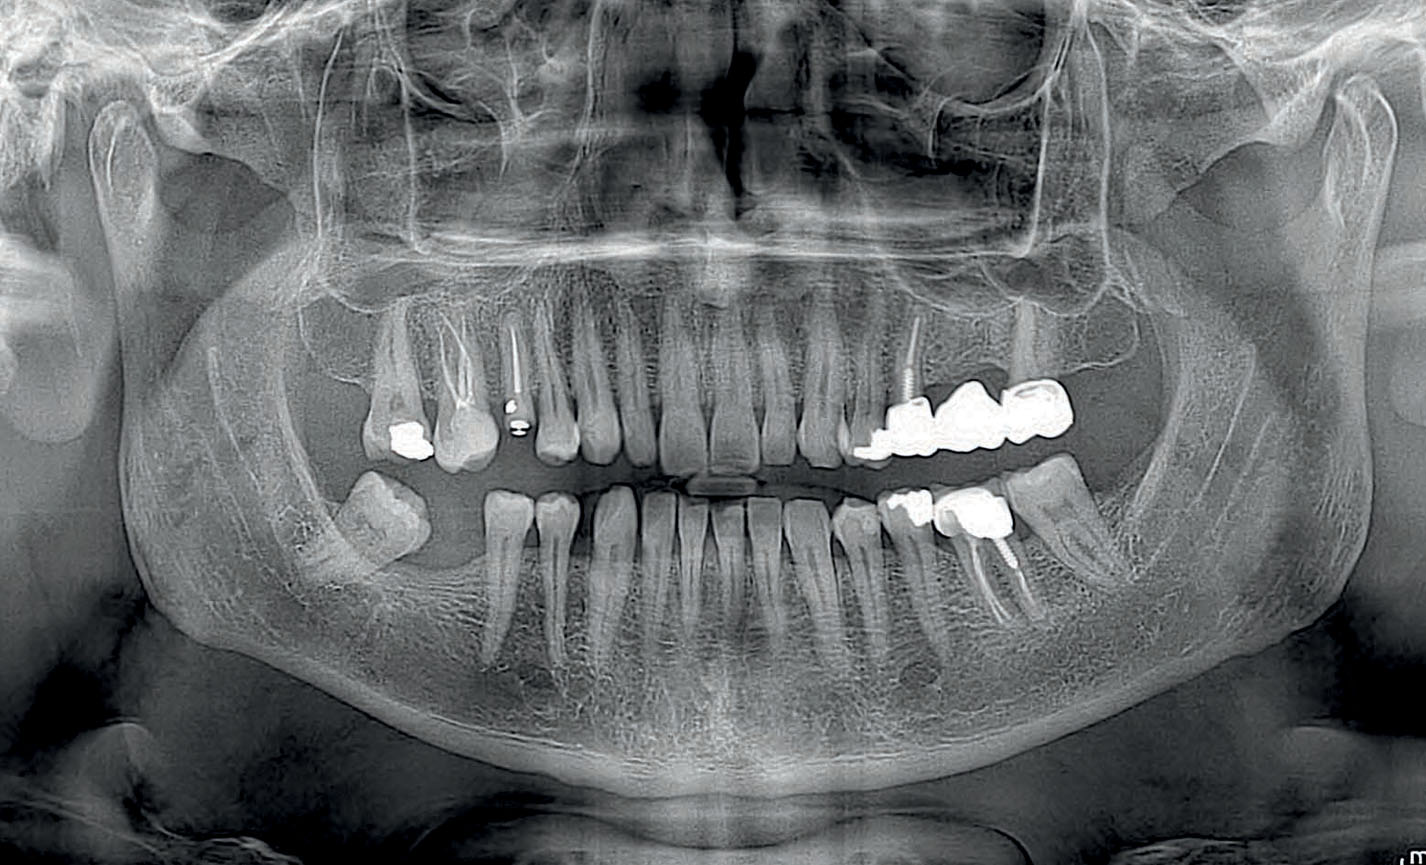

Tiszta kép mosolyáról gyors és fájdalommentes panoráma röntgen!

Láss tisztán! Precíz diagnózist panoráma röntgennel, modern technika pontos eredmények – panoráma röntgen percek alatt.  Rendelőnkben egy minden igényt kielégítő digitális Myray Hyperion X5 panoráma röntgen áll rendelkezésre.

Tudta, hogy egy pontos diagnózis kulcsa a részletes képalkotás? Panoráma röntgen segítségével teljes képet kaphat fogai és állkapcsa állapotáról – gyorsan, biztonságosan és fájdalommentesen. Keressen minket bizalommal és gondoskodunk mosolya egészségéről!

panoráma röntgen felvétel